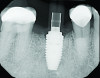

Case Presentation

Fig 1. Immediate implant placement with a PEEK healing abutment to contour soft tissue, mandibular right first molar.

Figure 1